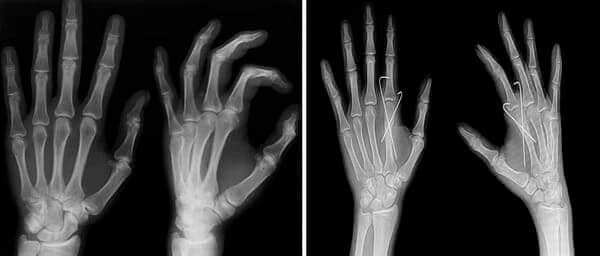

Schauen Sie sich an, was in meinem Kopf angekommen ist und was er nach Hondro Sol geworden ist. Ich dachte, ich würde für den Rest meines Lebens leiden, aber dieses Spray hat mich gerettet und mir die Möglichkeit gegeben, das Leben in vollen Zügen zu genießen.